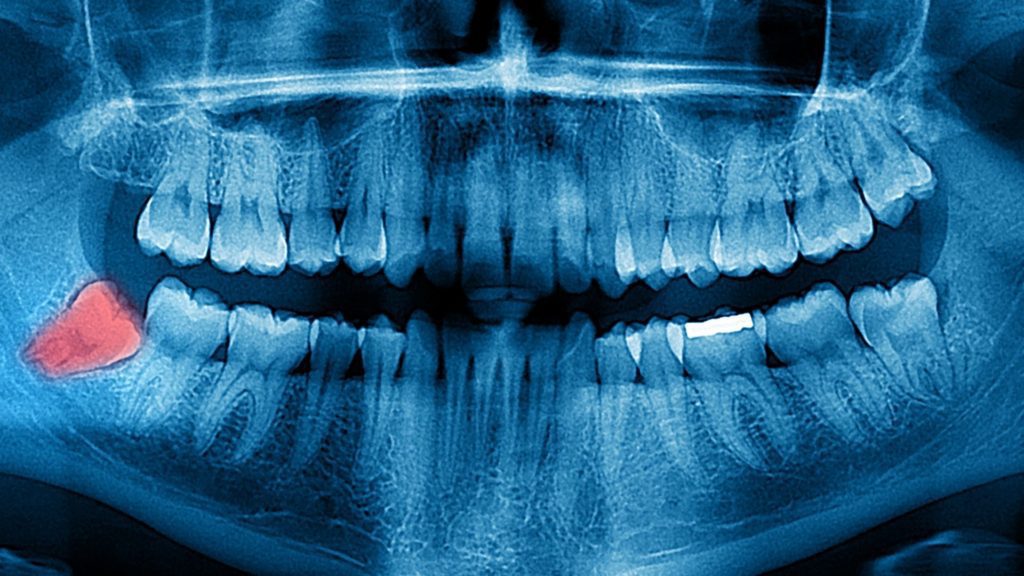

Imagen Dental Intraoral. La tecnología en el campo odontológico ha ido evolucionando a lo largo del tiempo ayudando tanto al odontólogo como a los pacientes a obtener mejores diagnósticos en menor tiempo y a mayor alcance de todos.